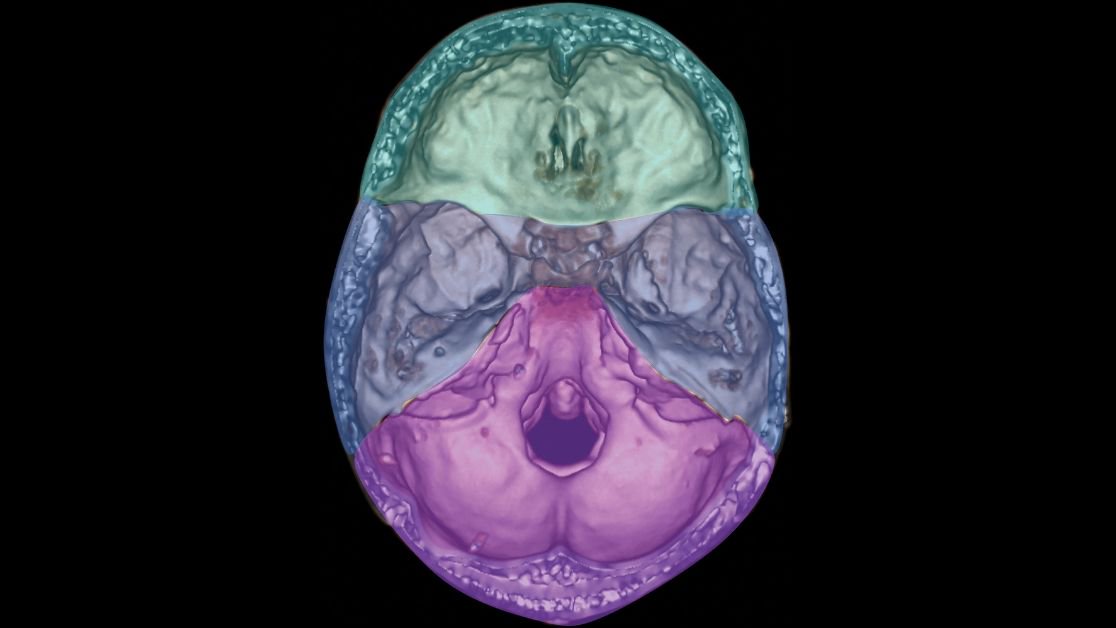

Dural sinus thrombosis on CT head with and without the bone removal